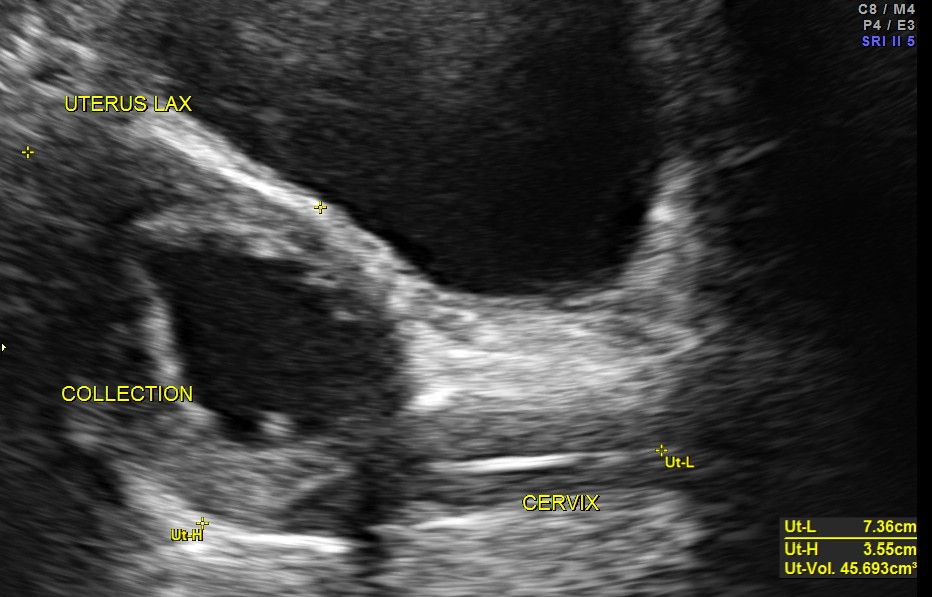

The pelvic scan had a surprise finding. Prominent fluid collection was seen in the endometrial cavity with echogenic cervix. ( She had no symptom of any vaginal bleeding or discharge )

The diagnosis was : acute calculous cholecystitis , cystic duct stones causing a rupture and fluid collection around the GB and loculated sub diaphragmatic collection with reactive mild right pleural effusion . Endometrial fluid collection needed further evaluation.